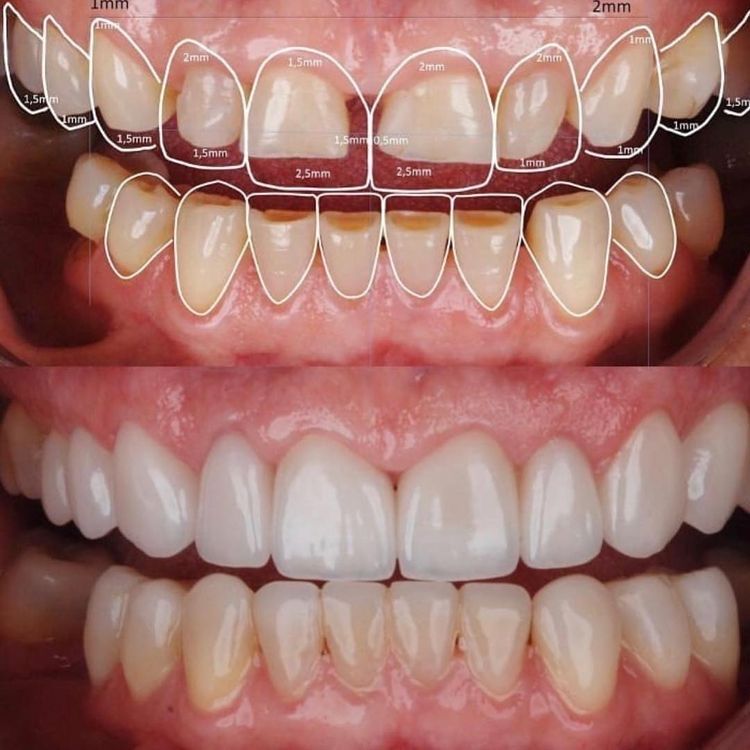

Casos de Prostodoncia

Nuestros casos documentados de antes y después muestran cómo corregimos dientes dañados, espacios, desgaste dental o problemas de color, logrando sonrisas estéticas y funcionales. Cada transformación refleja nuestro compromiso con la precisión, la calidad y la satisfacción del paciente.